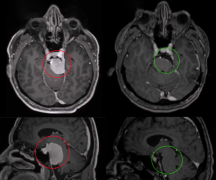

影像